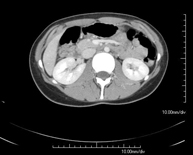

Prova diagnòstica que consisteix en l'estudi de l'abdomen d'alta definició anatòmica (fetge, vesícula biliar, via biliar, pàncrees, melsa, estómac, intestins, ronyons, estructures vasculars, bufeta, úter i ovaris, etc.) mitjançant l'ús d'un equip de TC (Tomografia Computeritzada). Aquestes imatges s'estudien posteriorment en una estació de treball que permet obtenir reconstruccions bidimensionals en diferents plànols de l'espai i també reconstruccions 3D (volumètriques). La majoria d'estudis requereixen l'ús de contrast iodat per millorar la definició de les imatges. - TC Pelvis

Prova diagnòstica que consisteix en obtenir imatges bi i tridimensionals de l'abdomen d'alta definició anatòmica (estructures òssies, estructures vasculars, fetge, pàncrees, vesícula biliar, ronyons, glàndules suprarenals, melsa, intestí prim i gros, bufeta, úter i ovaris, pròstata i vesícules seminals, urèters, etc.) mitjançant l'ús d'un equip de TC (Tomografia Computeritzada). La majoria d'estudis requereixen l'ús de contrast iodat. - TC Fetge

Prueba diagnóstica que consiste en obtener imágenes del abdomen de alta definición anatómica (hígado, vesícula biliar, vía biliar, páncreas, bazo, estómago, intestinos, riñones, estructuras vasculares, vejiga, útero y ovarios, etc.) mediante el empleo de un equipo de TC (Tomografía Computarizada). Dichas imágenes se estudian posteriormente en una estación de trabajo que permite reconstrucciones bidimensionales en diferentes planos del espacio, y también reconstrucciones 3D (volumétricas). La mayoría de estudios requieren el empleo de contraste yodado para mejorar la definición de las imágenes. - TC Estudio rotacional EEII